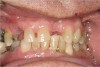

Figure 10a  Supra-eruption of the opposing arch, thus diminishing crown height space.

Figure 10a

Figure 10b  Supra-eruption of the opposing arch, thus diminishing crown height space.

Figure 10b